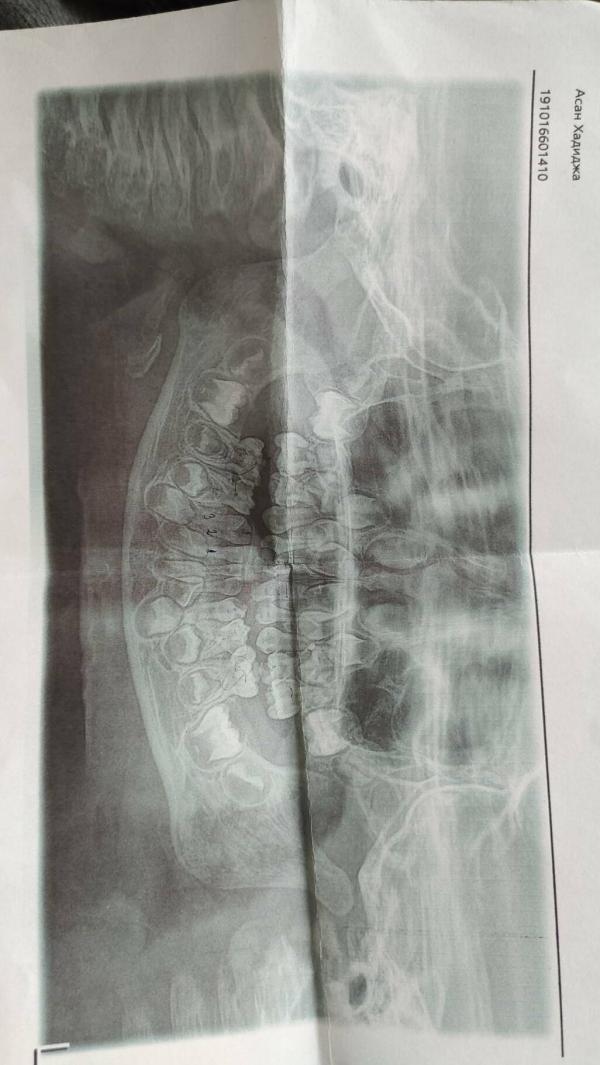

@alyona0419 Спасибо, азот как вариант, ребенок хоть в сознании. Кто-то говорит 5 зубов, кто-то 16. Каждый доктор по своему видит, нужно будет ещё перед лечением хороший снимок зубов сделать.